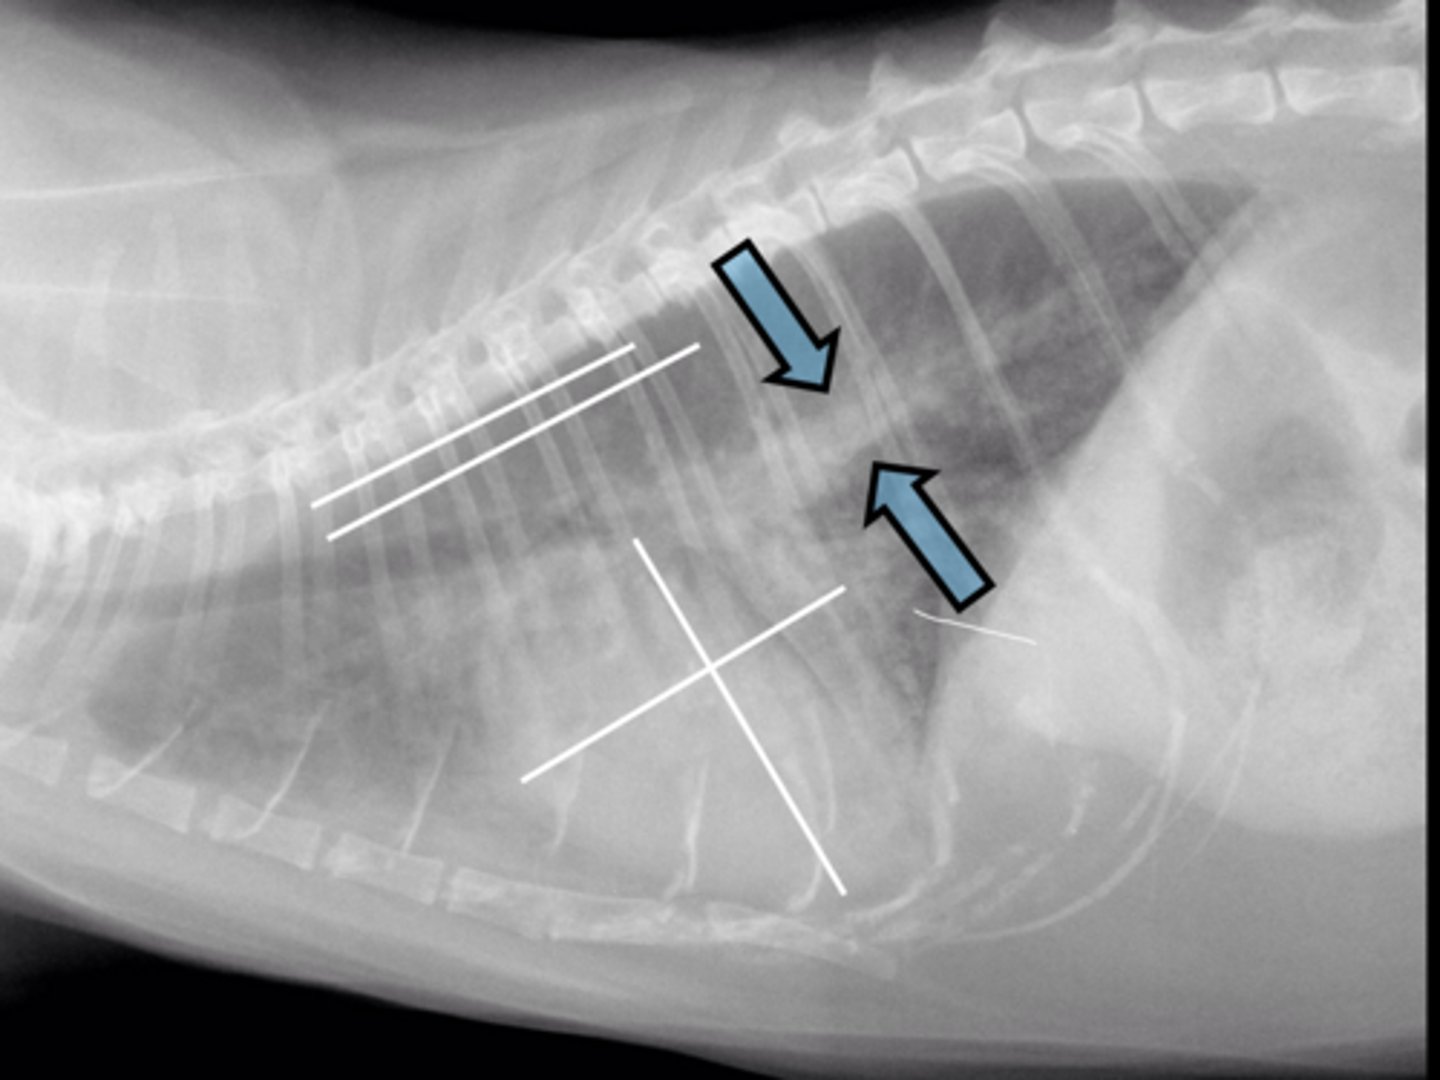

Good correlation between heart size and body length

What is VHS based on?

Corina to apex (excluding pericardial fat)

What are landmarks of the length portion of the VHS?

Perpendicular to length axis lining up w/ caudal vena cava

What are landmarks of the width portion of the VHS?

t4

What vertebra do we start measuring the VHS?